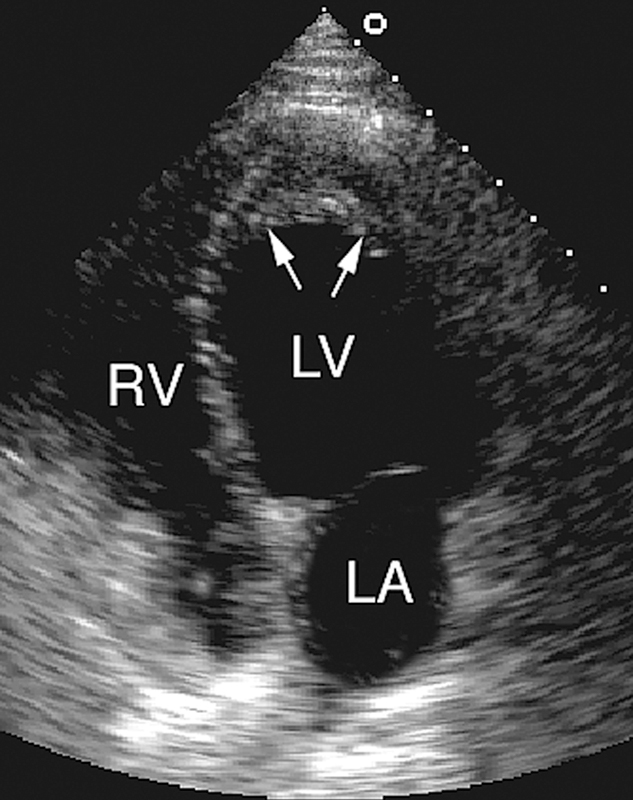

فحوصات تشخيصية لبعض امراض القلب والشرايين التاجية